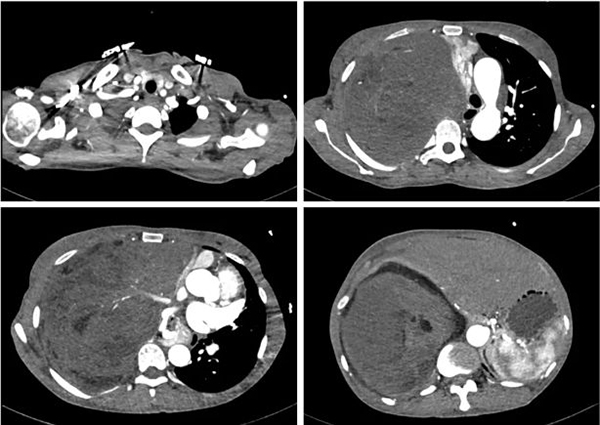

患者术前胸部CT检查

入院CT报告提示:右侧胸腔可见巨大混杂密度肿块,大小约为30*17*17cm。(红色虚线标记范围为巨大胸腔肿瘤)

经过多方打听,玛合帕丽了解到省立医院刘相燕主任医师团队在复杂纵隔肿瘤的手术治疗方面有着丰富的经验。此前,刘相燕主任已完成多例复杂纵隔肿瘤的外科治疗,但肿瘤生长到如此体积确实罕见:患者胸部CT显示肿瘤长径达30厘米,完全占据右侧胸腔,心脏也被挤压到了一旁。患者既往病理诊断为脂肪肉瘤,经过两个周期的化疗,肿瘤体积不降反增。胸腔巨大恶性肿瘤且对化疗不敏感,日渐增长的肿瘤导致患者病情继续恶化,随时可能有生命危险,手术切除成为当前治疗的唯一方法。与此同时,手术存在巨大的风险:肿瘤体积巨大导致手术操作空间极小、肿瘤血供丰富且侵袭性强,稍有不慎会导致不可控制的大出血、肿瘤长期压迫导致心脏移位,一旦肿瘤切除可能会影响血液循环稳定甚至心跳骤停……一系列的风险对手术团队提出了巨大挑战。但患者面对疾病的痛苦和绝望,以及家属对团队的无条件信任,让刘相燕主任医师团队下定决心挽救这个濒临破碎的家庭。